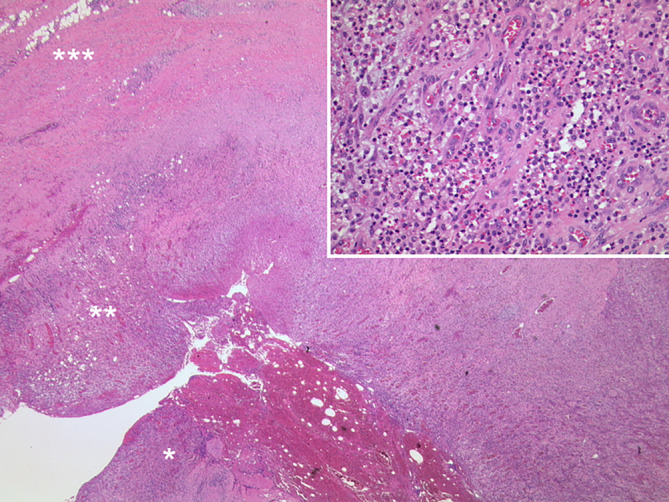

Abstract Image